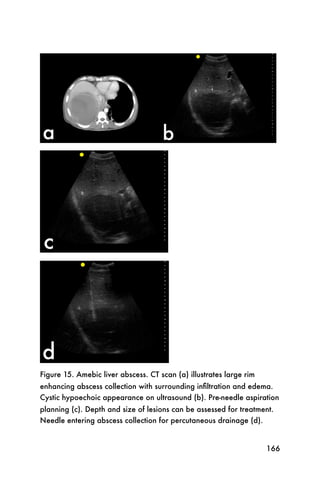

191

Figure 9. The porta hepatis composed of the gallbladder (GB), the

portal vein (*), and the common bile duct (arrow)

It may help to perform the exam with the patient in left

lateral decubitus position, as shown in Figure 10.

192

Figure 10. Left lateral decubitus position for gallbladder scan

193

After the porta hepatis is identified, rotate the probe 90

degrees to identify the porta hepatis in a longitudinal